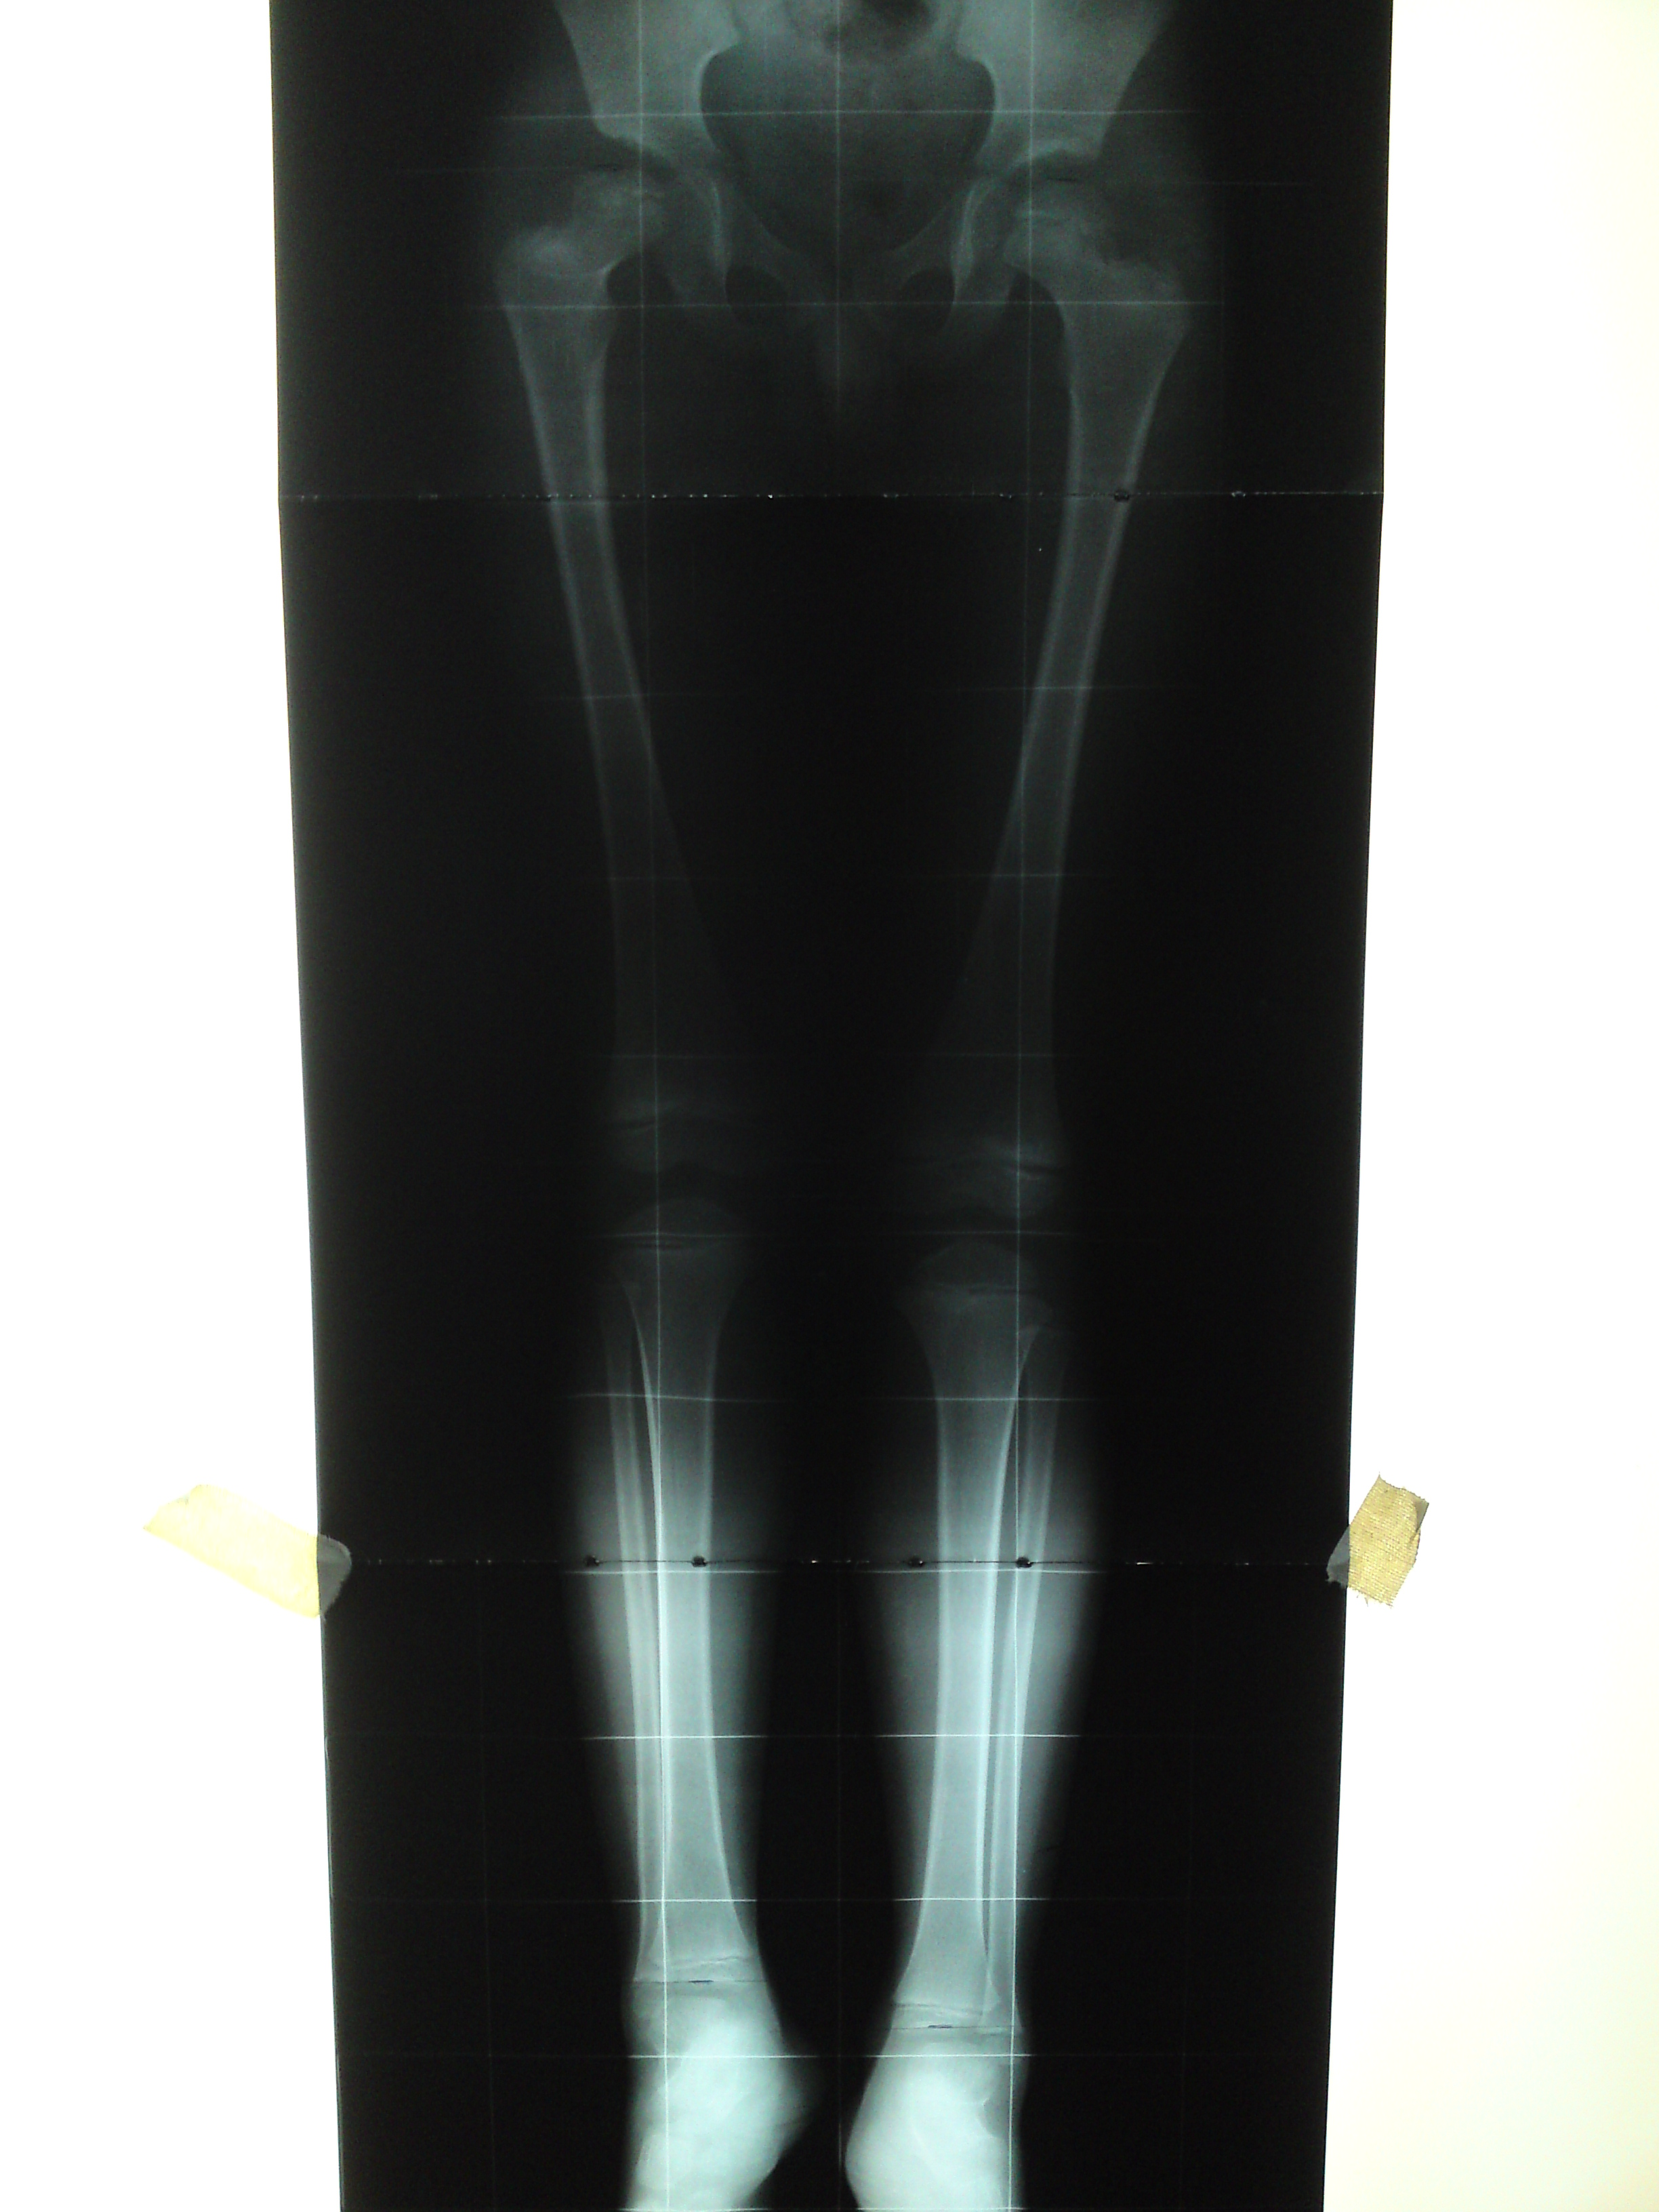

Modulación del crecimiento en osteodistrofia renal. [Growth modulation in renal osteodystrophy]

3. Barrett IR, Papadimitriou DG. Skeletal disorders in children with renal failure. J Pediatr Orthop 1996;16(2):264-72.

4. Oppenheim WL, Fischer SR, Salusky IB. Surgical correction of angular deformity of the knee in children with renal osteodystrophy. J Pediatr Orthop 1997;17:41-9.

5. Castañeda P, Urquhart B, Sullivan E, Haynes RJ. Hemiepiphysiodesis for the correction of angular deformity about the knee. J Pediatr Orthop 2008;28(2):188-91.

14. Stevens P, Klatt JB. Guided growth for pathological physes: radiographic improvement during realignment. J Pediatr Orthop 2008;28(6):632-9.